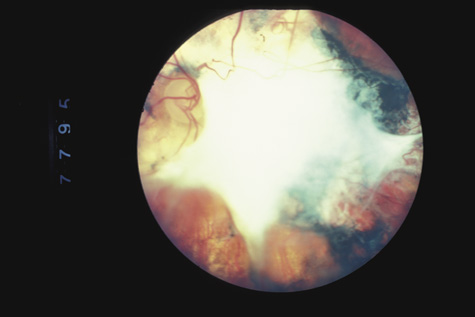

Fig. 11. A: Serous detachment of the macula and intraretinal and vitreous hemorrhage after the eye was struck with a baseball. B: Three months later. The hemorrhages have cleared, revealing severe pigment epithelial necrosis. The visual acuity is counting fingers.

The visual acuity in commotio retinae varies from 20/20 to 20/400 and does not always correlate with the degree of retinal opacification. There is no known treatment. The prognosis is usually excellent except in cases with associated subfoveolar choroidal rupture and in cases with choroidal rupture with subfoveolar hemorrhage. Poor visual recovery can also be expected in cases with severe retinal pigment epithelial damage. Serous retinal detachment (Fig. 11) signals this condition, which can be confirmed by leakage of fluorescein into the subretinal space.70